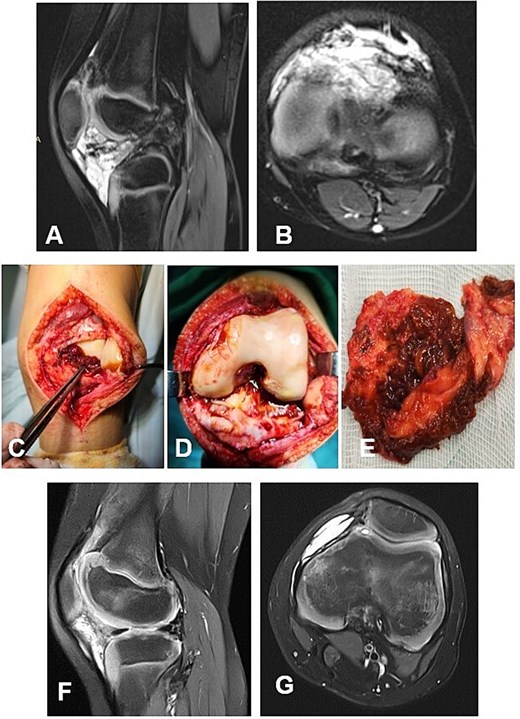

А 16-year-old female athlete presented with knee effusion and pain without preceding trauma, persisting for 3 months. Diagnostic MRI revealed an intra-articular, retrocondylar mass with intact cruciate ligaments and menisci (Fig. 6A and B). The lesion was identified as a nodular tenosynovial giant cell tumor and was excised through a posterior partial synovectomy using a medial approach with lateral retraction of the m. gastrocnemius medialis. The tumor was removed sharply and en bloc within macroscopically healthy synovial margins (Fig. 6C–E). At the 12-month postoperative follow-up, the patient was asymptomatic, with no MRI evidence of local recurrence (Fig. 6F and G). Successful return to full athletic activity.

Case 5. (A and B) Preoperative sag and ax MRI TSE PD FS—lobulated edematosus intra-articular neoplasm with a posterior mediocentral localization. (C and D) Posterior synovectomy between m. semitendinosus and m. gastrognemius medialis. (Е) Macroscopic appearance of the N-TGCT measuring 3 × 2 × 2 cm after excision. (F and G) Postoperative 12 m. Sag and Ax MRI TSE PD FS—no evidence of recurrence of the resected neoplasm. PD FS, proton density weighting with fat suppression; TSE, turbo spin echo.